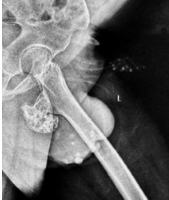

Soft-tissue dissection included carefully incising the sinus tract created during the biopsy through its entire length. The surgical field was circumferentially lined with hydrogen-peroxide soaked mops as a form of chemical cauterization, and two separate trolleys were maintained – one for instruments contaminated with tumor material and the other for sterile instruments. After adequate exposure, tumor material was scooped out with a curette, with the tumor cells carefully removed using a high- speed burr to achieve negative margins. Utmost care was taken to not breach the anterior or medial wall of the proximal humerus while using the burr under fluoroscopic guidance. A final hydrogen-peroxide wash was given. Reconstruction of the void started with a basal layer of tri-cortical iliac crest bone graft. Under fluoroscopic guidance, 4 fully-threaded cancellous screws were then inserted in a pre-determined sequence of different orthogonal plains to create a scaffold (2 in rostro-caudal manner, 1 antero-posterior, and 1 transverse) (Fig.3) .

Figure 3: Cancellous screw scaffold created in the tumor void.